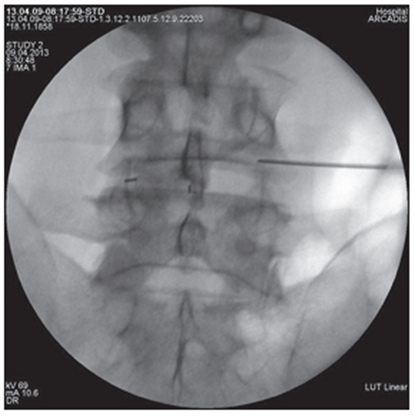

Figure 3. Lumbar intraoperative radiograph spine in direct projection. The tip of the puncture needle is located in the LIV-V intervertebral foramen on the right along the medial pedicular line |